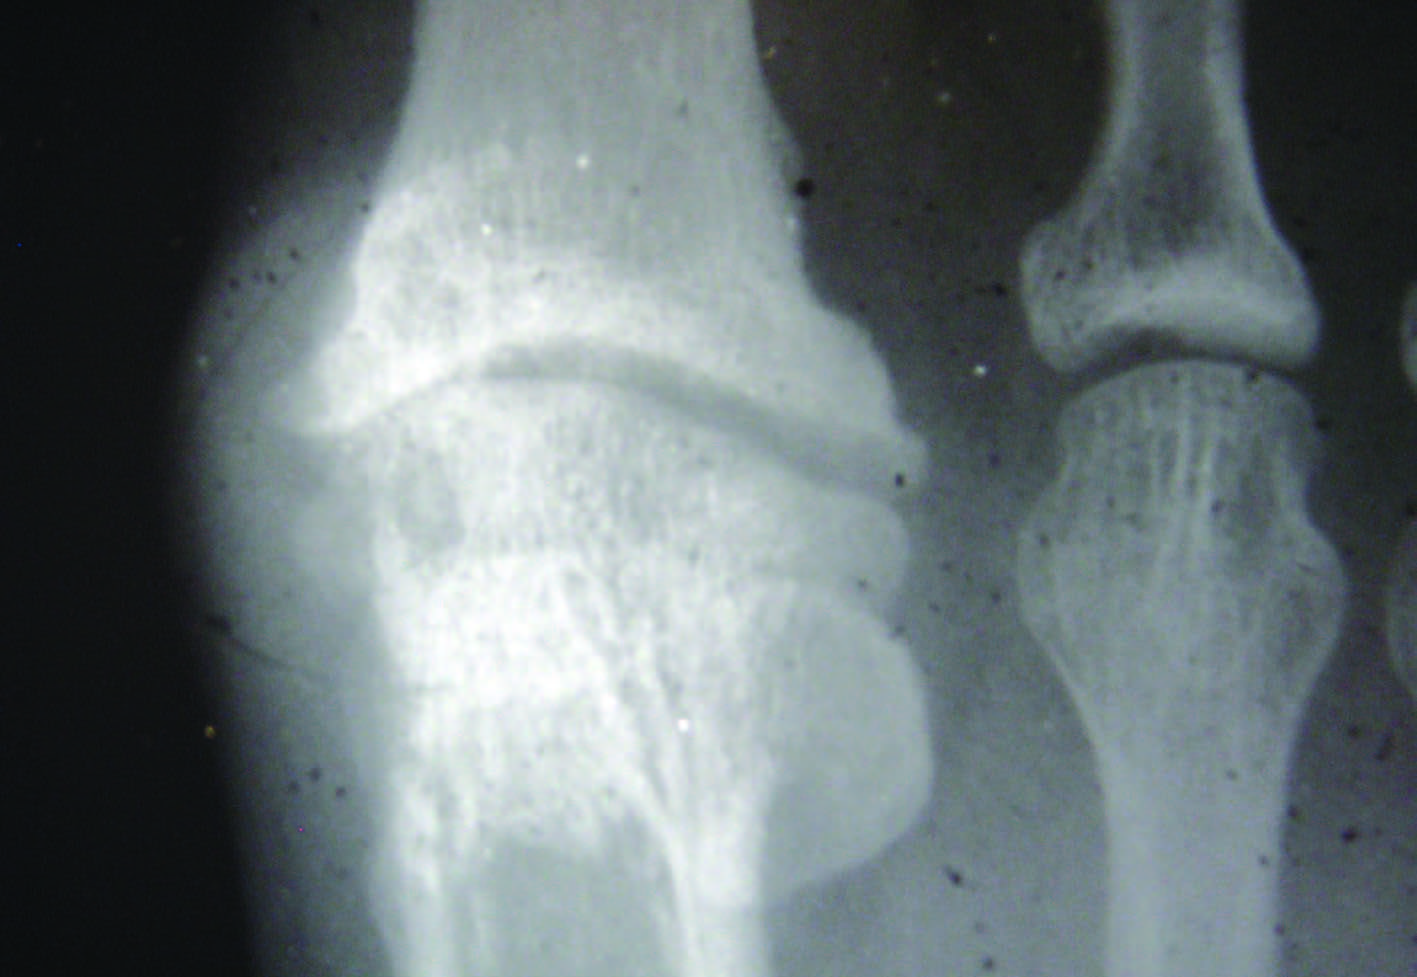

X-rays may display degeneration and excess bone growth at the MTP joint. These may include ice and oral anti-inflammatory medications. They aim at raising your metatarsal joints so that they dont suffer injuries resulting from pressure exerted by your foot.